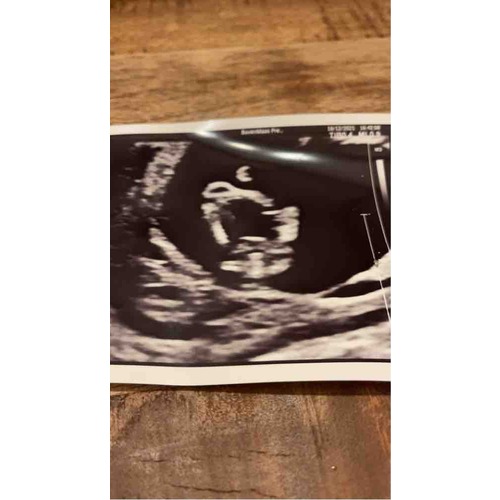

Ik heb ook een sterk vermoeden dat het een jongen is

Denk een jongen

Ja ik twijfel dus heel erg, omdat het "los" lijkt van het lichaam.

Zo zag het bij ons eruit (een meisje), dus ik denk bij jullie een jongen!

Ja maar bij ons kindje kan het ook de navelstreng zijn uiteraard. Het blijft spannend!

Om heel eerlijk te zijn lijkt het mij erg groot voor een geslachtsdeel en z ...

Precies, net wat ik ook dacht.

Dit is absoluut de navelstreng!! Ik snap niet dat mensen hier 100% jongen t ...

Ja precies. Ik hecht er ook nog geen waarde aan hoor! 😬 Ik zie het wel bij de geslachtsecho

Wat leuk, gefeliciteerd! Dus toch de navelstreng hè?

Jep! De navelstreng zat tussen de beentjes haha!